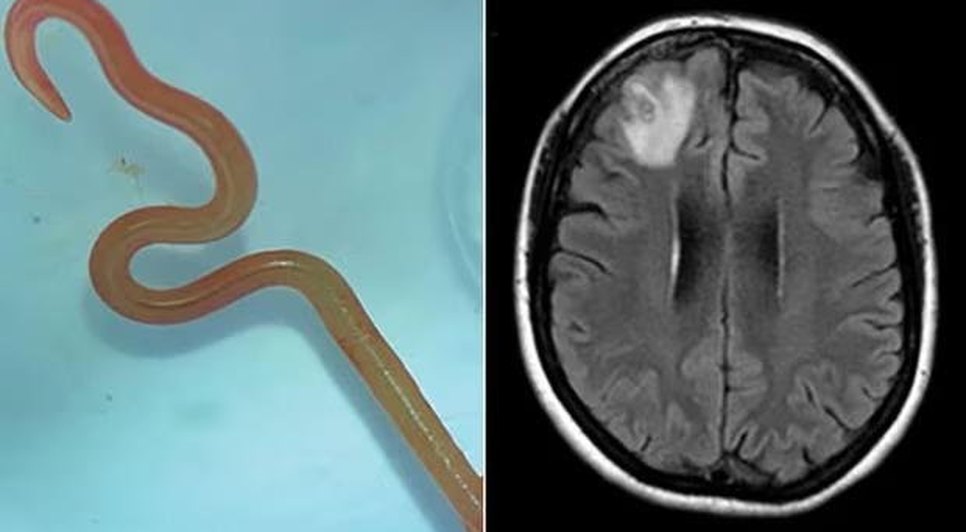

Os médicos encontraram uma lesão no lobo frontal direito, durante uma ressonância magnética. Quando a biopsia foi realizada, encontraram o verme, de cerca de 8cm. A região onde a paciente mora é habitada pelas cobras Pítons, comuns na Austrália.